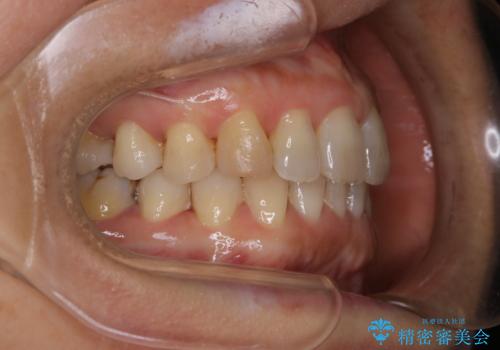

- 上下の歯のがたつきと、噛み合わせが深いことを気にされてご相談にいらした方です。噛み合わせに参加していない歯を抜歯してインビザラインにて治療を行いました。

一般的に噛み合わせの深い方へのインビザライン治療は適応が難しいとされていますが、今回は噛む力を上手にコントロールできたことと、内側に入り込んでいた前歯の角度を調整したことで下の歯がしっかり見えるようになりました。短期間で劇的に見た目が改善し、大変喜んでいただけました。